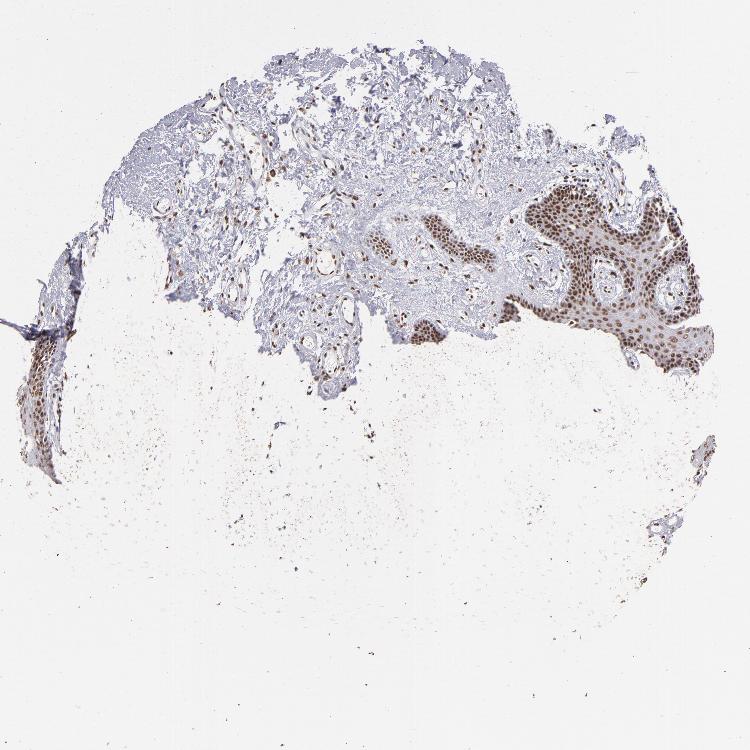

TISSUE PRIMARY DATA ORAL MUCOSA Show tissue menu

ORAL MUCOSA - Antibody stainingi

Antibody staining in the annotated cell types in the current human tissue is reported as not detected, low, medium, or high, based on conventional immunohistochemistry profiling in selected tissues. This score is based on the combination of the staining intensity and fraction of stained cells.

Each image is clickable and will lead to virtual microscopy that enables deeper exploration of all samples and also displays staining intensity scores, fraction scores and subcellular localization as well as patient and tissue information for each sample.

Antibody HPA001853Antibody HPA012292Antibody CAB000330

Squamous epithelial cells MediumLowLow